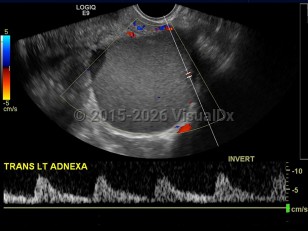

EndometriosisEndometriosis

Ovarian cancerOvarian cancer

Uterine fibroidsUterine fibroids